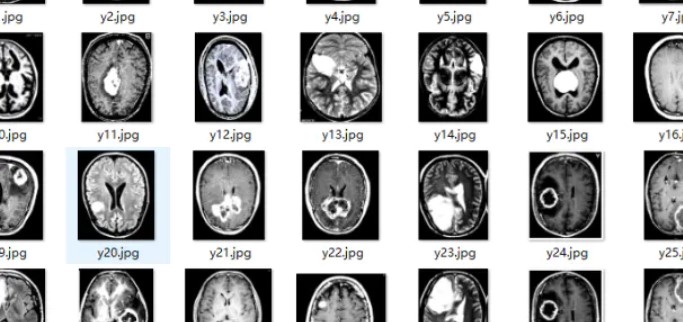

医学图像脑肿瘤区域检测数据集(yolo)

可检测医学图像中的脑肿瘤区域

训练集500张、验证集201张